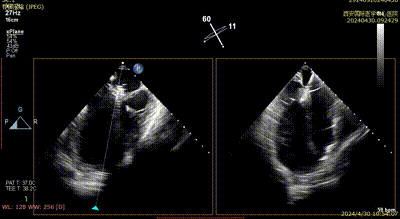

患者为75岁女性,因间断性心慌气短8个月,加重两月入院,既往腔隙性脑梗塞,乳腺癌30年,已治愈。心脏彩超提示:前叶长度:2.9cm,后叶长度:1.2cm,瓣口面积:4.5cm²,病变宽度:13mm。

心脏瓣膜介入团队术中在2区植入一枚二尖瓣夹,关闭二尖瓣夹时时刻关注瓣叶张力,并随时释放张力。患者术后反流降至1+,跨瓣压差为3mmHg。

Case 2影像资料

术后二尖瓣反流评估

术后结果